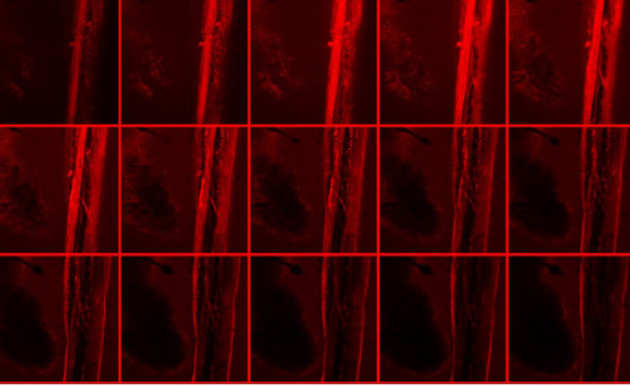

By studying the role of the vagal system in the control of energy metabolism - understanding which nerve signals suppress or elicit food satiety - we can design efficient treatments for obesity.

By studying the role of the vagal system in the control of energy metabolism - understanding which nerve signals suppress or elicit food satiety - we can design efficient treatments for obesity.

We aim to develop an accurate system for detection, stimulation and recording of chemical and electrical changes in the vagus nerve in response to physiological stimulation of gut hormones and nutrients.